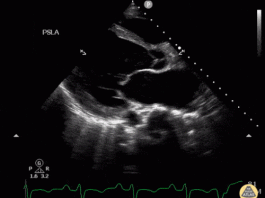

54 Yaş Göğüs Ağrısı Erkek Hasta

Hasta Bilgisi

Yaş / Cinsiyet: 58 yaşında erkekBaşvuru Nedeni: Ani başlayan göğüs ağrısı

Birincil Değerlendirme

Bilinç: Açık, koopere

Solunum: Hafif dispneik, solunum sayısı 22/dk

Dolaşım: Soğuk,...